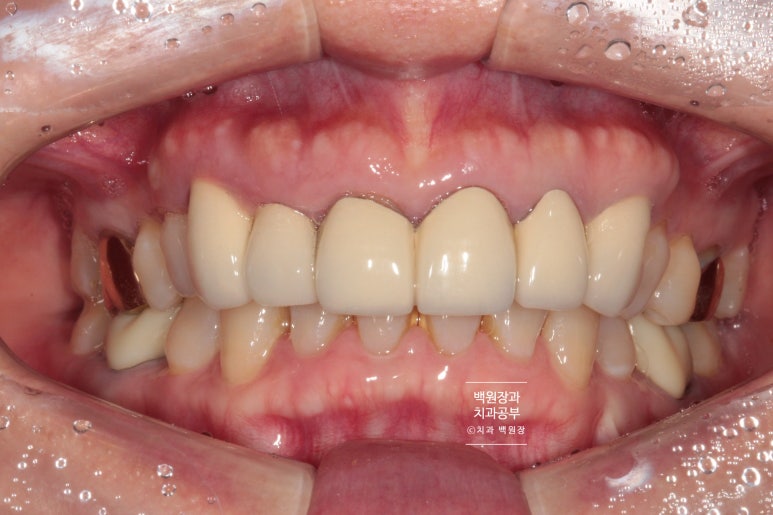

이렇게 봤을 때는 큰 문제가 없어보이는 앞니를 가진 환자분이었습니다.

아래 앞니에 치석이 조금 보이지만... 그리고 위 앞니에 크라운 치료를 받으시고 오래되서 뿌리 노출이 조금 있긴 하지만, 기능적으로 큰 문제는 없어보이죠?